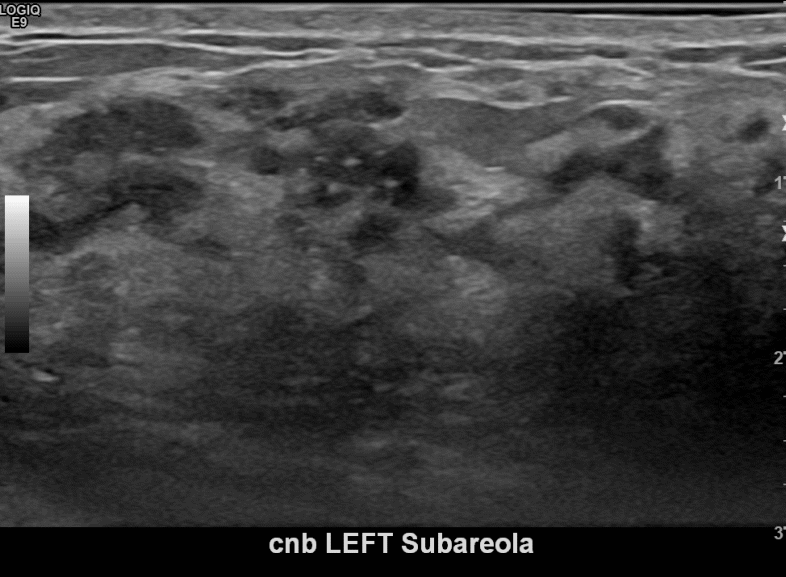

상기환자 건진상 이상소견으로 조직검사권유받고 내원하신 40대 여성분으로 좌측유방멍울  조직검사시행후 유방암 진단되었습니다.